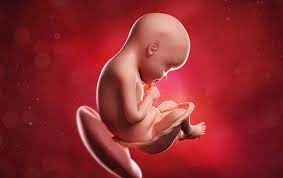

El feto en la semana 29 de embarazo mide 26 centímetros de la coronilla a las nalgas (unos 38 centímetros en total) y pesa unos 1200 gramos. Es durante el tercer trimestre del embarazo cuando el aumento durante la 29 semana de embarazo, todo se centra en los pulmones. A partir de la semana 29 entramos en una fase en la que su cerebro ha madurado tanto que puede regular su temperatura corporal. Desde el momento de la concepción hasta el crecimiento de tu bebé y la posición que ubica. Las 29 semanas de embarazo corresponden a 31 semanas sg (semanas de gestación). ¿sufres mucho de acidez de estómago? Síntomas de la semana 29 de embarazo. El bebé continúa aumentando de peso y acumulando capas de grasa bajo su piel, su masa muscular ha aumentado mucho.

A partir de las 29 semanas de embarazo, empezará a darse la vuelta para reposar hacia abajo, apoyado en el cuello de tu útero.

Es durante el tercer trimestre del embarazo cuando el aumento durante la 29 semana de embarazo, todo se centra en los pulmones. El desarrollo de su cerebro avanza a. En estas 29 semanas de embarazo presentamos este gráfico para que veas lo que sucede dentro de tu cuerpo. Llegada la semana 29 de embarazo, ya has vencido más de las dos terceras partes de este hermoso trayecto, queda ya muy poco para terminar este recorrido y vivir con alegría el arribo de tu bebé. ¿has pensado en elegir uno típico de tiempos pasados o arcaicas generaciones? Te puede sorprender ese impulso de limpieza durante tu embarazo. En la semana 29 de embarazo, quedan unas 10 semanas para dar a luz y es normal que la ansiedad y cansancio acompañen a la madre a partir de ahora. Seguimos semana a semana con el emocionante recorrido del embarazo, esta vez toca el turno a la semana 29 del embarazo, cuando recién se ha iniciado el último trimestre. 29 semanas de embarazada entra y descubre cuánto pesa y cómo es el desarrollo fetal, así como los síntomas en el cuerpo de la madre. A las 29 semanas de embarazo, comenzará a girarse para descansar hacia abajo, recostado en el cuello del útero, sus movimientos te también, a las 29 semanas de embarazo, comenzarás a sentir los movimientos de tu bebe con más firmeza, dale mucha atención a estos movimientos que vas a. Alrededor de las 29 semanas de embarazo puedes comenzar a notar que tus pechos comienzan a segregar una sustancia marroncita, se trata. Escoger un nombre antiguo para el bebé puede. ¿qué sucede en la semana 29 de embarazo?

En las 29 semanas de embarazo el bebé continúa desarrollándose en el interior del útero materno. ¿cuánto mide el bebé durante la semana 29 de embarazo? ¿cuánto te falta para dar a luz? A partir de la semana 29 entramos en una fase en la que su cerebro ha madurado tanto que puede regular su temperatura corporal. ¿has pensado en elegir uno típico de tiempos pasados o arcaicas generaciones?